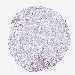

LIVER CANCER - Protein expressioni

A mouse-over function shows sample information and annotation data. Click on an image to view it in a full screen mode. Samples can be filtered based on level of antibody staining by selecting one or several of the following categories: high, medium, low and not detected. The assay and annotation is described here.

Note that samples used for immunohistochemistry by the Human Protein Atlas do not correspond to samples in the TCGA dataset.

Antibody stainingi

Antibody staining in the annotated cell types in the current human tissue is reported as not detected, low, medium, or high, based on conventional immunohistochemistry profiling in selected tissues. This score is based on the combination of the staining intensity and fraction of stained cells.

Each image is clickable and will lead to virtual microscopy that enables deeper exploration of all samples and also displays staining intensity scores, fraction scores and subcellular localization as well as patient and tissue information for each sample.

Antibody HPA019062

Antibody HPA043230

Staining

High

Medium

Low

Not detected

Intensity

Strong

Moderate

Weak

Negative

Quantity

>75%

75%-25%

<25%

None

Location

Nuclear

Cytoplasmic/membranous

Cytoplasmic/membranous,nuclear

Cholangiocarcinoma

Carcinoma, Hepatocellular, NOS